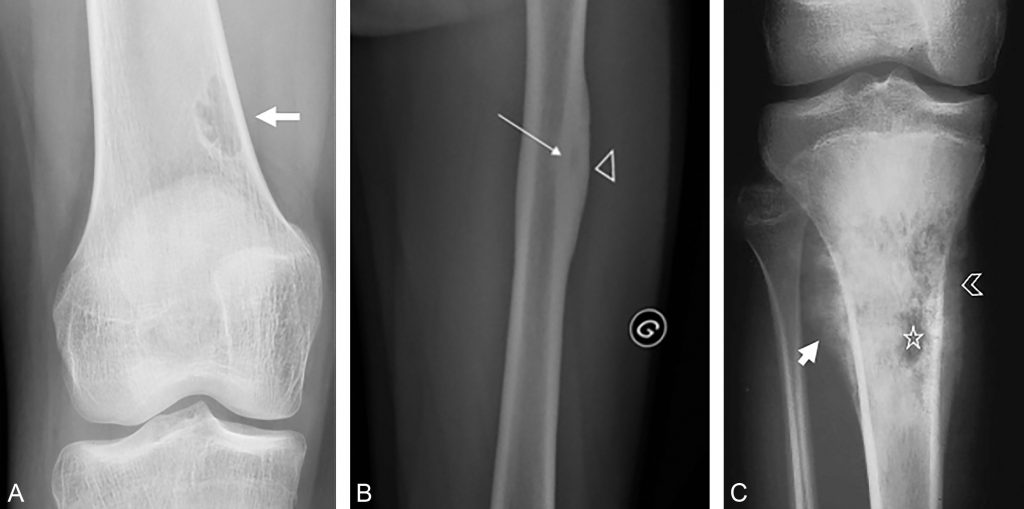

Fig. 87.1 Exemple de tumeurs osseuses primitives.

(A) Fibrome non ossifiant « don’t-touch-lesion » : radiographie du fémur de face, lésion ostéolytique avec sclérose périphérique de topographie métaphysaire excentrée d’aspect multilobulée dont le grand axe est parallèle à celui de la diaphyse fémorale. Il n’y a pas d’envahissement des parties molles ni d’apposition périostée. (B) Ostéome ostéoïde : radiographie du fémur de face, épaississement cortical fusiforme (tête de flèche), développé dans l’axe du fémur centré par une lacune intracorticale ovalaire appelé nidus (flèche). (C) Ostéosarcome : radiographie du genou de face, ostéolyse agressive perméative excentrée (étoile) de la métaphyse supérieure du tibia avec envahissement des parties molles (tête de flèche) et réaction périostée agressive en « feu d’herbe » (flèche).

Source : CERF, CNEBMN, 2022.